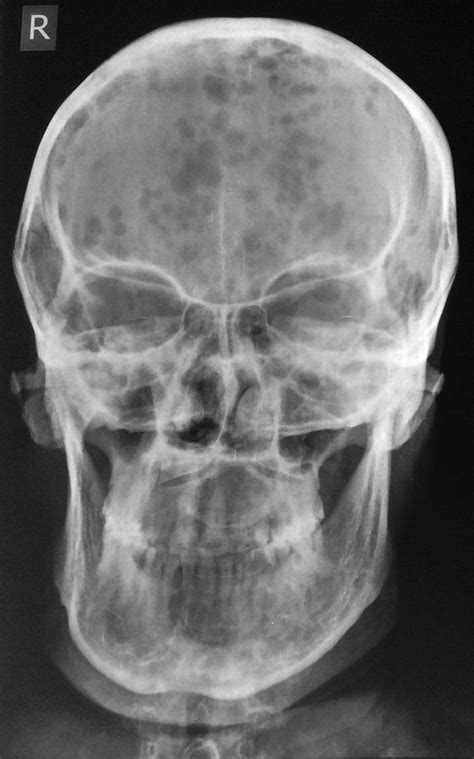

Marie deswarte, dvm, decvdi, dacvrobserving osteolytic lesions on radiographs is one of the four diagnostic criteria for multiple myeloma, so this modality plays an important role in the clinical. The recently updated durie/salmon plus staging system published in 2006 highlights the many advances that have been made in the imaging of multiple myeloma, a common malignancy of plasma cells. Osteoporosis is most common skeletal abnormality in this disease. This pattern has the most adverse prognosis. For this reason, imaging plays a major role in the management of disease in patients with mm. It once was considered in the same spectrum of plasma cell dyscrasias with polyneuropathy as poems syndrome but is now considered a separate entity. It may manifest as multiple sclerotic lesions or areas of diffuse osteosclerosis 3. International myeloma working group consensus statement and guidelines regarding the current role of imaging techniques in. Multiple myeloma imaging, that is to say using imaging studies such as mri to identify mm activity, is central to managing our mm. Osteoporosis, osteoclastic destructions, pathological fractures of the bone, spinal cord and compression can impair patients' quality of life and reduce survival. Multiple myeloma (mm), the second most common hematologic malignancy, is characterized by clonal proliferation of plasma cells. Multiple myeloma is a malignant proliferation of the plasma cells mainly affecting bone marrow, but other organs may also be involved. Dr mohammad taghi niknejad and dr ki yap et al.

The most common location is in the axial skeleton (spine, skull, pelvis and ribs) and in the diaphysis of long bones (femur and humerus). Gadolinioum (gd), according to the study linked below, encourages the growth of multiple myeloma. Gd is the agent that enhances the contrast of the many mri scans you will have during your life as a mm survivor. Marie deswarte provides the radiology perspective on this multiple myeloma case. It arises from red marrow due to the monoclonal proliferation of plasma cells and manifests in a wide range of radiographic abnormalities. In multiple myeloma, when the cancer protein level is up, the normal antibody levels are down. Multiple lytic 'punched out' lesions. Multiple myeloma (mm) is a clonal plasma cell proliferative disorder characterized by primary infiltration of bone marrow and excessive production of abnormal immunoglobulin.

Multiple myeloma is a blood cancer affecting the plasma cells of the bone marrow. Many clinical studies suggest modern imaging techniques for their greater. Multiple myeloma is characterized clinically by osseous involvement favoring the axial skeleton with associated pain and sequelae, hypercalcemia, chronic renal insufficiency, anemia, and the presence of monoclonal immunoglobulin (ig, m protein) in serum and/or urine. In multiple studies, including autopsy series 1, 9 and studies based on imaging findings , investigators have reported that the reticuloendothelial system is most commonly affected by extraosseous myeloma.one autopsy series reported splenic, hepatic, and lymph node involvement in 31%, 29%, and 23%, respectively, of patients with myeloma. Osteosclerosing (or osteosclerotic) myeloma is an uncommon form of multiple myeloma. Discussion multiple myeloma (mm) is a neoplastic proliferation of monoclonal plasma cells within the bone marrow. It is used to establish the diagnosis and to dictate the immediate need for therapy. Dr mohammad taghi niknejad and dr ki yap et al. Multiple lytic 'punched out' lesions. Multiple myeloma is a type of blood cancer arising from the uncontrolled clonal proliferation of malignant plasma cells resulting in impaired hematopoiesis, hyper production of monoclonal protein, bone tissue destruction leading and renal system alterations up to kidney failure. It once was considered in the same spectrum of plasma cell dyscrasias with polyneuropathy as poems syndrome but is now considered a separate entity. Distinctive to mm are the lucent, elliptical, subcortical shadows, especially in long. Lesions are usually multiple and found in vertebrae, ribs, skull, pelvis, and femur.

Lesions are usually multiple and found in vertebrae, ribs, skull, pelvis, and femur.